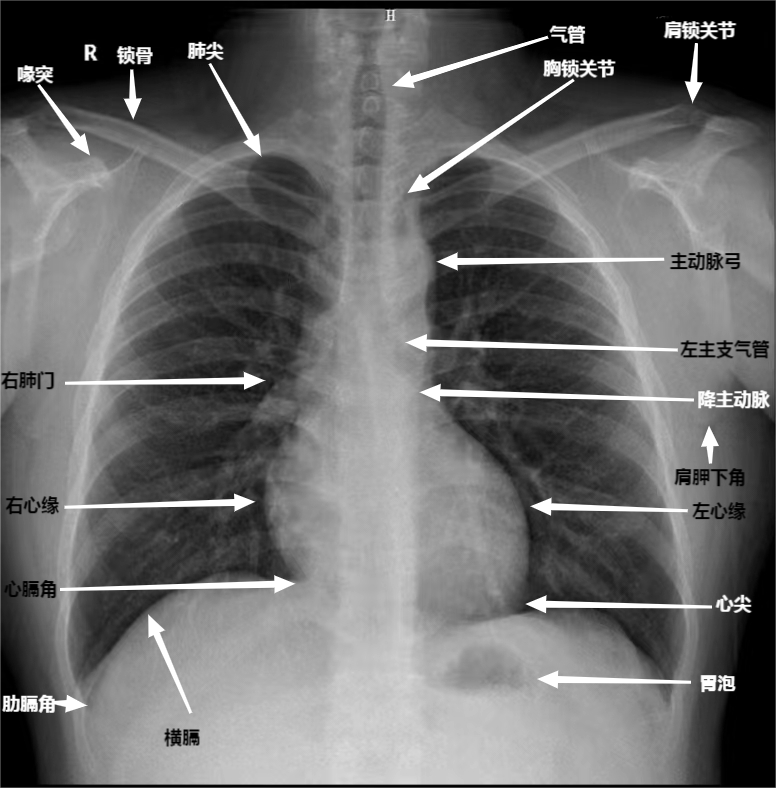

④标准影像显示部位:(1)肺尖充分显示;(2)两侧胸锁关节对称;(3)肩胛骨投影于肺野之外;(4)肺门阴影结构可辨;(5)锁骨、乳腺、左心影内可分辨出肺纹理;(6)心脏、纵膈边缘清晰锐利;(7)膈肌包括完全,且边缘锐利。如下:

DR胶片为什么分尺寸借DR成像原理详解胸部正位摄片技术参数_https://www.jmylbn.com_新闻资讯_第3张